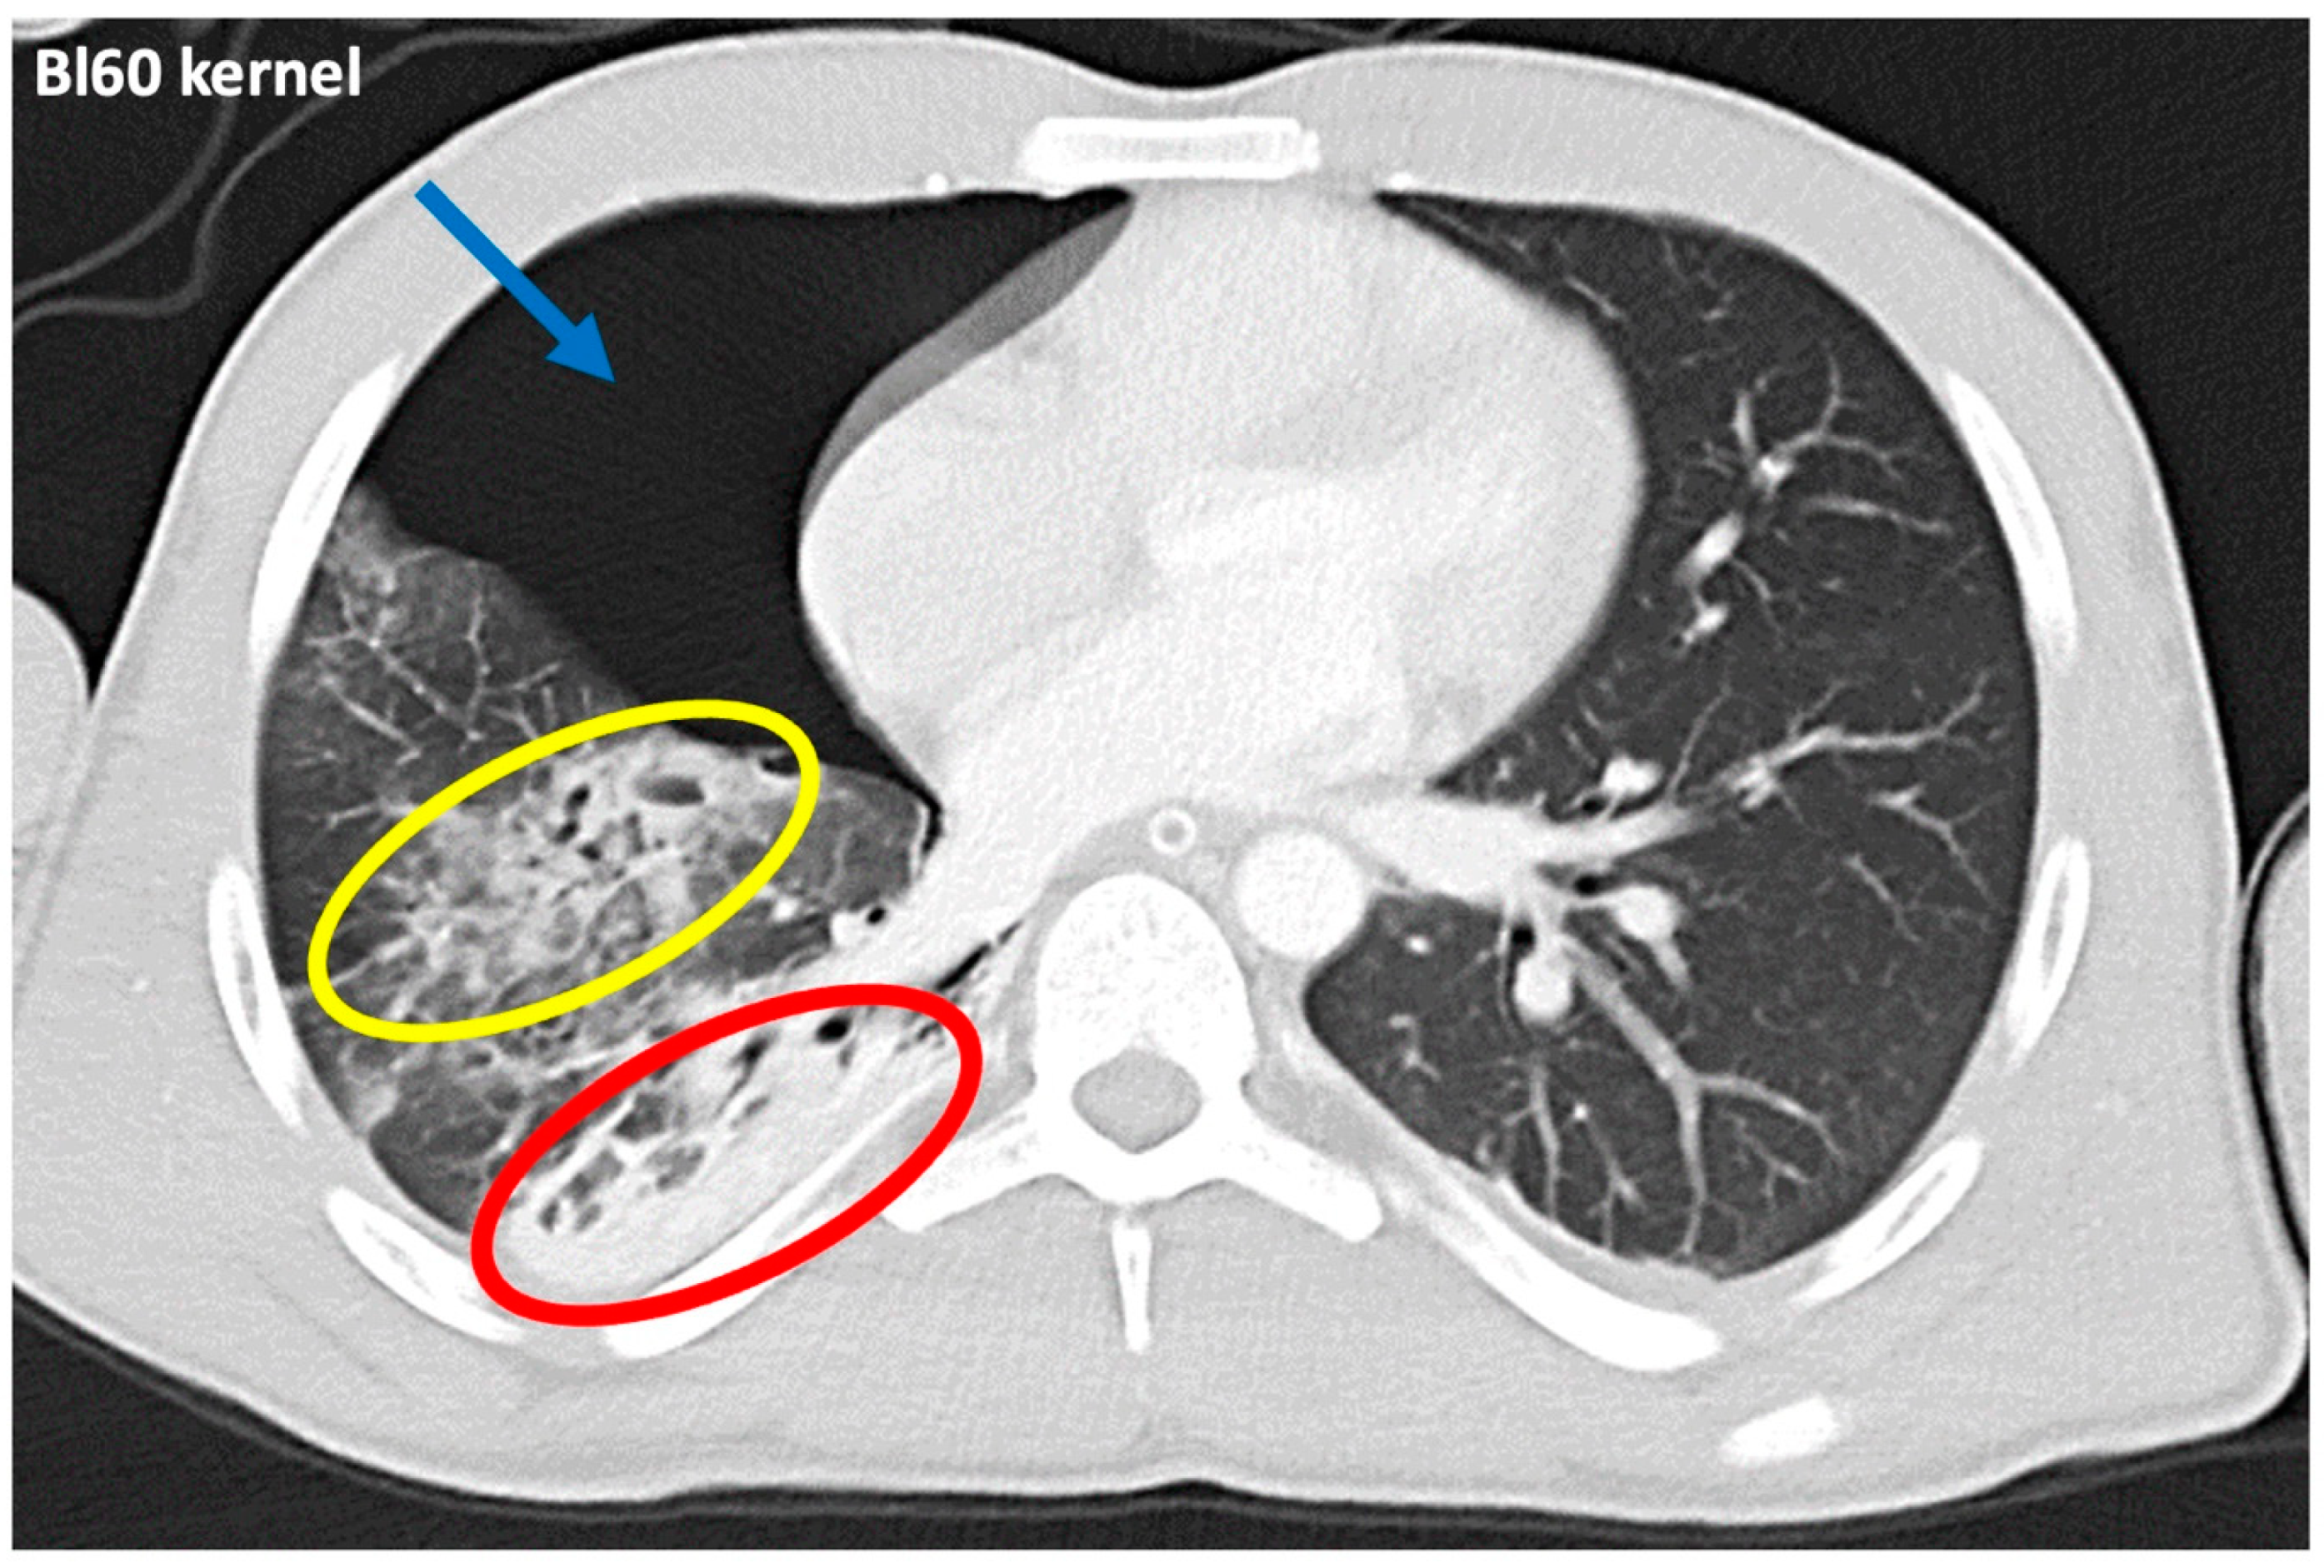

2.4. Objective and Subjective Image Parameters

3.3. Qualitative Image Analysis